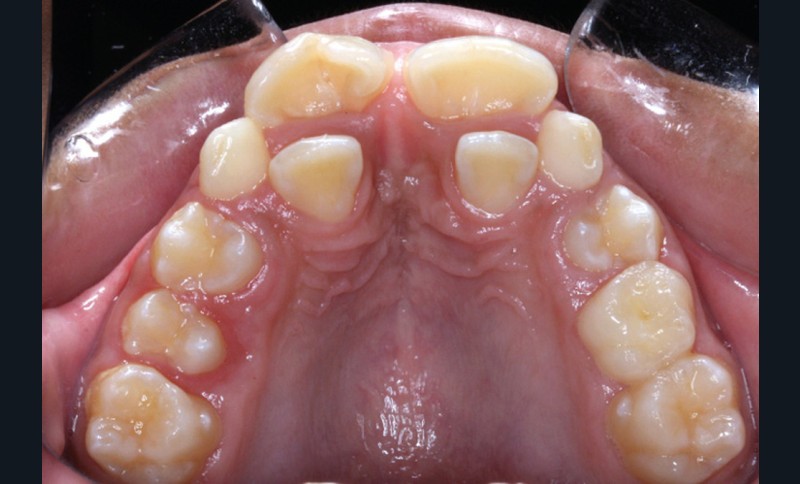

Antony, 11 ans se présente initialement pour une demande esthétique concernant ses deux incisives centrales qu’il trouve trop grosses (fig. 1a-c).

Le profil est convexe et associé à une inocclusion labiale au repos. Il s’agit d’une classe II squelettique sur un schéma facial normodivergent. Les rapports occlusaux sont de classe II bilatérale (complète au niveau molaire) avec des incisives inférieures vestibulo-versées. La 21 est géminée et la 11 vraisemblablement fusionnée avec un germe surnuméraire, sans altération de la formule dentaire. Du fait du diamètre mésiodistal fortement augmenté des incisives centrales, et du manque de place à l’arcade maxillaire qui en découle, les 12 et 22 sont en inversé d’occlusion en palato position. Les 53 et 63 sont persistantes sur l’arcade avec une inclusion en transposition incomplète de la 13, dont la cuspide se situe entre la racine de la 12 et celle de la 11 résorbée (fig. 1d-g).